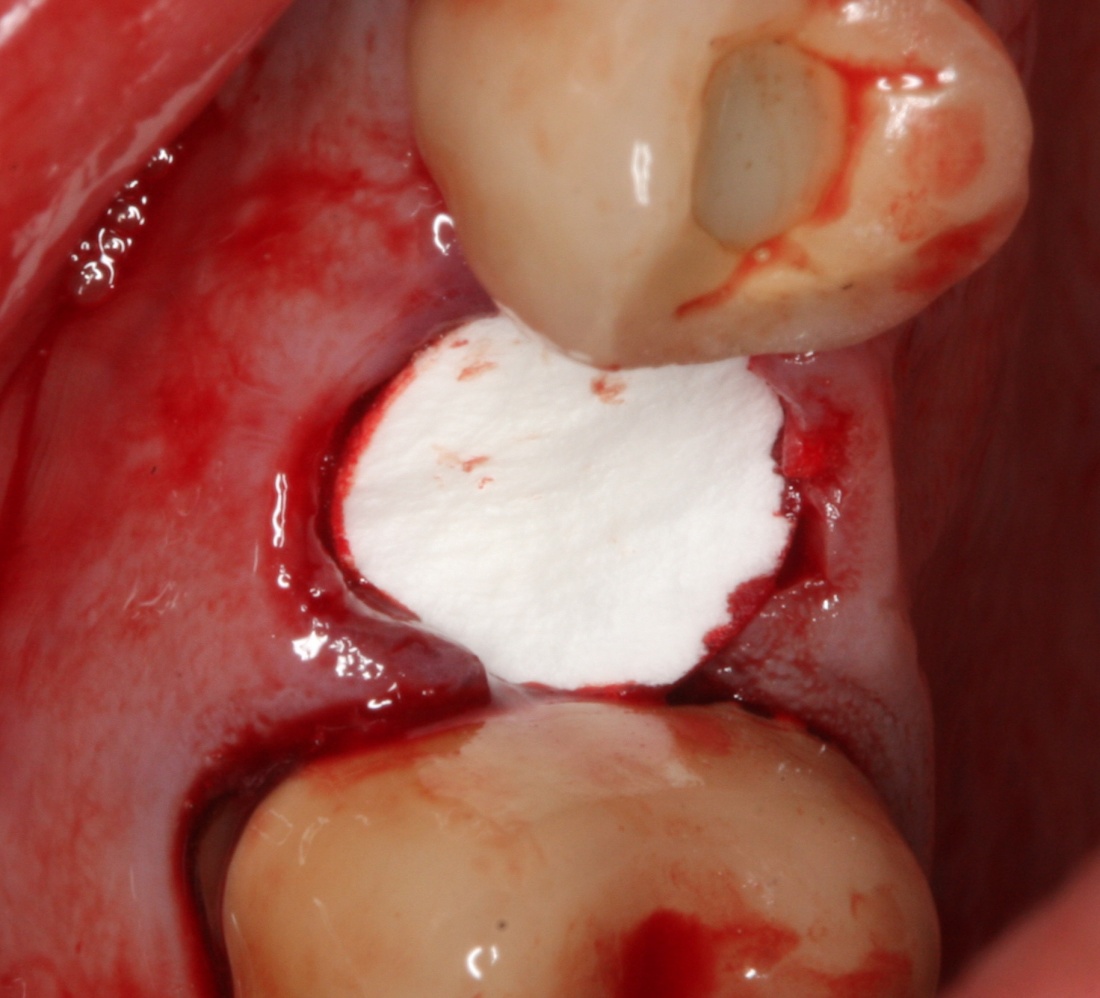

Изоляция области аутографта и имплантатов барьерной мембраной.

Перекрывать костный блок барьерной мембраной или оставить так? По этому вопросу есть много мнений. Между тем, в публикации по методике есть ясное показание, когда это требуется.

Конкретно в этом клиническом случае между костным аутотрансплантатом, ложем и имплантатами есть пустое пространство. Если его не изолировать от мягких тканей, они прорастут и осложнят интеграцию аутографта. Поэтому я решил перекрыть костный блок барьерной мембраной, пусть это делает хирургическую операцию немного дороже.

На этом этапе есть несколько нюансов, о которых я хочу рассказать отдельно.

— я использовал барьерную мембрану Geistlich Bio-Gide, которая имеет две разные поверхности: с одной стороны она рыхлая «адгезивная», с другой — гладкая и прочная. Как укладывать — на результат не влияет, но в плане удобства рыхлую поверхность мы «приклеиваем» к тому, на чем требуется барьерную мембрану удержать. В данном случае хотелось бы удержать её на костной поверхности — следовательно, мы укладываем её рыхлой поверхностью к кости.

Ремарка: примечательно, что во время синуслифтинга ситуация иная - там требуется удержать барьерную мембрану на слизистой оболочке верхнечелюстной пазухи. Следовательно, рыхлая поверхность - на стороне шнайдеровой мембраны.

— много лет мы используем антибиотики для интраоперационной профилактики инфекционно-воспалительных осложнений. Уже в то время мы пришли к выводу, что удобнее всего — порошки антибактериальных препаратов для приготовления раствором: дешевые, стерильные, в удобной упаковке. Прямо в виде порошка их можно добавлять в графт, растворы для ирригации, либо использовать так, как показано на фото. Еще мы используем порошок антибиотика для изготовления пасты, которой обрабатываем имплантаты в процессе ревизии или при лечении периимплантита. Это удобнее и эффективнее, чем интраоперационное использование жидких форм антибактериальных препаратов.

— ты знаешь, что барьерная мембрана может выполнять две функции, каркасную и изолирующую. Первая функция требует обязательной фиксации и натяжения, вторая — нет. В нашем случае «каркасом» регенерата является костный блок, а барьерная мембрана нужна только для изоляции. Поэтому она не требует натяжения и фиксации пинами.

После я внимательно проверил, что костный блок и имплантаты полностью перекрыты. Теперь рану можно ушивать.